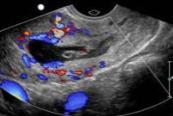

- Illustration 12. Transvaginal ultrasound showing peritrophoblastic blood flow on color Doppler suggesting implantation of the gestational sac into the cervix.